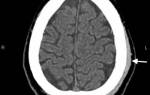

Лечением ушибов занимается хирург или травматолог. Для постановки диагноза врач проводит визуальный осмотр и ориентируется на клинические признаки. Гематомы внутренних органов можно обнаружить с помощью компьютерной томографии или МРТ.